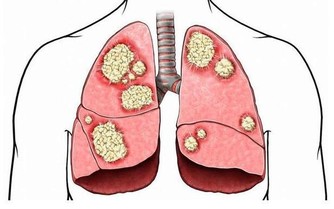

在夏天的悶熱過後,很快就迎來了秋天的涼爽與乾燥,老百姓都知道秋天是比較乾燥的季節,這個時期,對於鼻子粘膜比較薄的人會出現鼻出血的情況,對於肺臟本身不是很好的人,容易在這個時期出現咳嗽的表現,這些其實都是秋燥傷害了人體正常的陰液分佈,導致的結果。